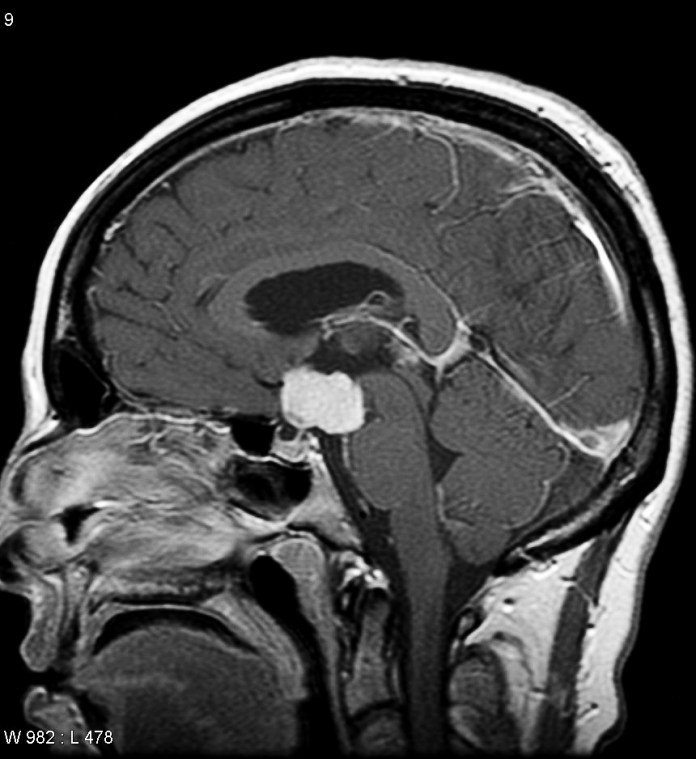

I began researching this project in June 2013 after marrying my wife, Pam, who has been a steadfast supporter, cheering me on along the way. I obtained medical records dating back to 1984 and incorporated journal entries from the early 1990s. So in many ways, I’ve been writing this memoir my whole life. The impetus to write the book sprang from a long blog post I wrote in December 2014 to mark the 30th anniversary of my initial brain surgery at SUNY Upstate Medical University Hospital in Syracuse, New York.

Set between 1984 and the mid–1990s, this coming-of-age memoir follows Francis DiClemente’s experience of adolescence and early adulthood in a body that struggled to develop. Diagnosed with a rare brain tumor that led to hypopituitarism, DiClemente remained physically underdeveloped while his peers matured into young adulthood. As he navigated relationships and sexuality in college, it became evident that his prolonged experience with physical nonconformity fueled isolation, self-doubt, and shame.

“DiClemente delivers an unflinching account of the brain tumor that disrupted normal growth and his participation in one of the first human growth hormone trials. …a touching and compelling memoir.”